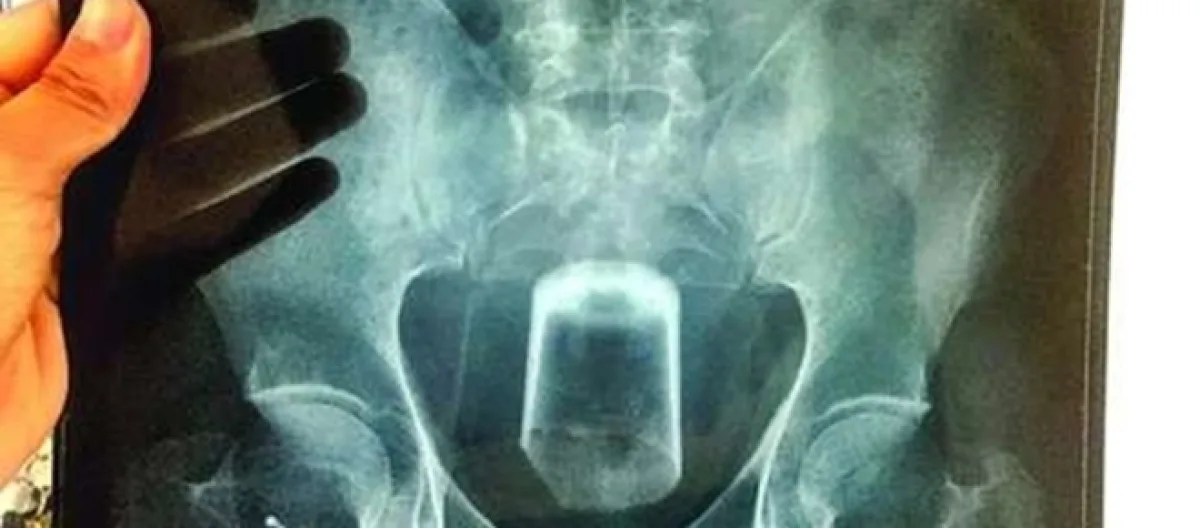

Os médicos confirmaram toda a história do homem através dos exames de raio x realizados. Era possível observar nitidamente a imagem do copo entalado na região do reto. Os profissionais do BMJ Case Reports afirmaram que o copo estava com a parte inferior para cima, ou seja, de cabeça para baixo. Os exames que foram realizados no italiano mostraram pequenos fragmentos de vidro dentro do organismo.